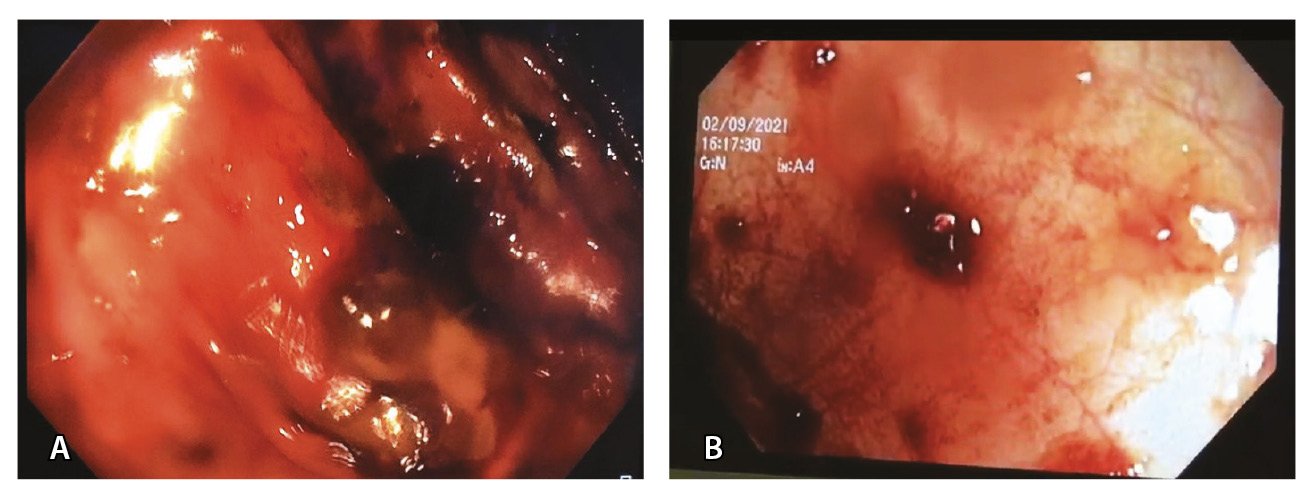

Рис. 1. Псевдомембранозный колит после перенесенной инфекции SARS-CoV-2. Возвышающиеся желтые псевдомембраны – в нисходящей ободочной кишке (А; больной 46 лет) и в поперечно-ободочной кишке (Б; больная 65 лет)

2. Fig. 1. Pseudomembranous colitis after SARS-CoV-2 infection. Elevated yellow pseudomembranes in the descending colon (А; a 46-years old patient) and in the transverse colon (B; a 65-year old patient)